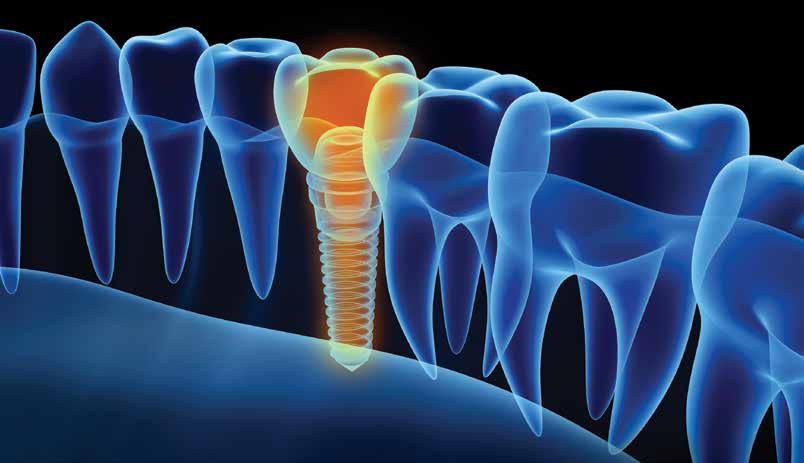

An Overview of Digital Workflows for Precision Impact Dentistry

ABSTRACT

Digital workflows in implant dentistry can help streamline and improve the quality of implant therapy by harnessing the power of cone beam computed tomography (CBCT), intraoral scanning, implant planning software, 3D printing and guided implant placement. This article provides an overview of the key steps and considerations for implementing digital implant dentistry for implant-supported fixed single or shortspan restorations using a static implant guide.

Digital implant workflows hold the promise for dentists to plan and execute implant placement with great accuracy, reliability and predictability, leading to potentially simpler and more predictable restoration.

Digital workflows in implant dentistry improve practice efficiency, procedure predictability and clinical outcomes. Digital implant planning aims to ensure that the implant is placed in a restoratively driven manner, while guided implant placement aims to ensure that the implant is placed exactly where it is digitally planned. Guided implant placement achieves higher accuracy and lower failure rates than freehanded or half- guided surgery because it provides a defined implant drilling and insertion path.1–3 Implants placed in such a manner are also more apt to be restored with screw-retained restorations, which leads to easier maintenance. By digitizing data, the implant planning process is sped up, physical storage space is decreased and patient chair time is decreased.1,4,5